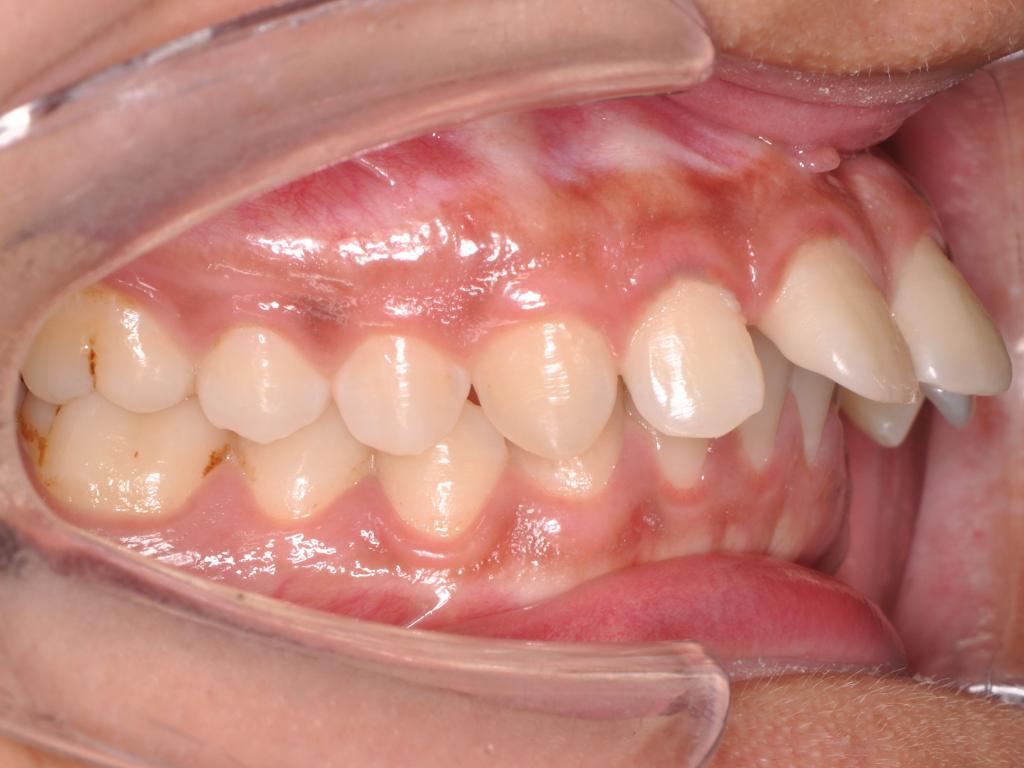

3. 前牙深覆合深覆盖

前牙深覆合是指上前牙覆盖下前牙唇面超过1/3,深覆盖是指上前牙的唇面与下前牙唇面之间的水平距离超过3mm,常常伴有下颌后缩,侧貌呈现凸面型。

矫治方法:前牙深覆合深覆盖的患儿常常伴有吮指,咬下唇,口呼吸等不良习惯,同样,应首先纠正其不良习惯,必要时可在其手指上涂抹苦瓜汁或是辅助矫治装置如唇挡丝、前庭盾等。同时早期可进行肌功能训练,如上唇肌张力训练。口呼吸习惯应进行耳鼻喉科会诊处理,检查其是否伴有鼻咽部疾病,排除鼻咽部疾病后,再使用前庭盾、闭口贴等纠正。针对功能性的因素,常用的矫治器为肌激动器,TB、FRⅡ。针对骨性的因素,常用的矫治器为头帽-肌激动器。